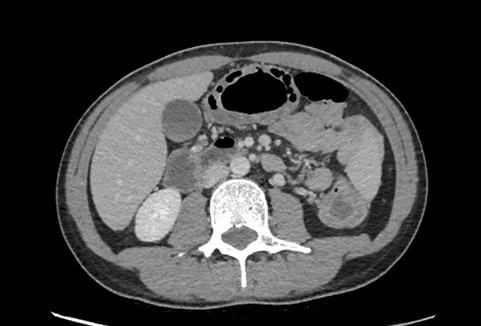

- Dépistage d’une complication : hémorragie massive, perforation ou mégacolon Le scanner abdomino-pelvien qui a désormais supplanté l’abdomen sans préparation dans cette situation est systématique. Il permet en outre d’apprécier l’étendue des lésions (Figure 1B).

Figure 1 B : ulcérations creusantes préperforatives du colon transverse observées en scanner au cours de la colite aiguë grave de rectocolite hémorragique